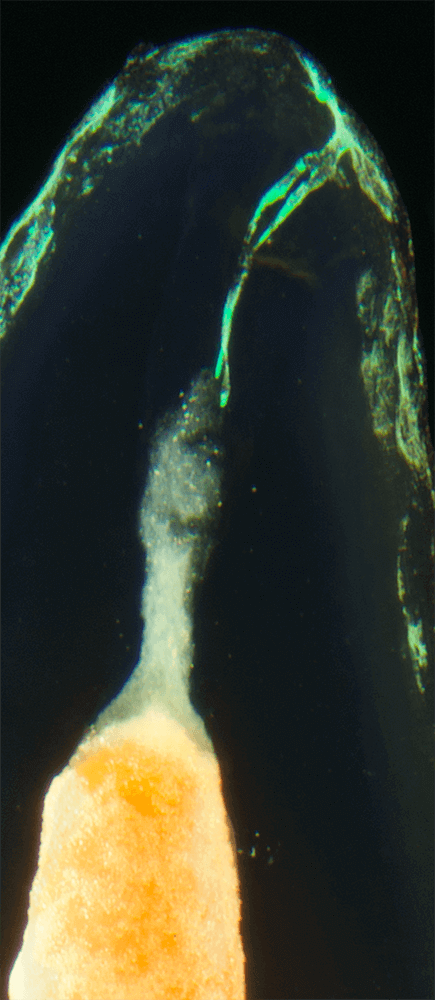

Das Verfahren, Zähne in durchsichtige Präparate zu überführen ist schon über 100 Jahre alt. Aber erst durch die Weiterentwicklung der alten Technik und die Kombination mit moderner Fotografie sowie der Entwicklung eines geeigneten Gefäßes zur Fotografie ist es meinem Vater Dr. Holm Reuver gelungen, einzigartige Bilder vom Inneren der Zähne aufzunehmen.

Die Bilder sind in verschiedenen Größen wählbar und auch als POPART-Variante erhältlich. Sie sind hervorragend geeignet für die Beratung von Patienten vor endodontischen Behandlungen, aber auch ein beliebter Eyecatcher im Wartezimmer. Außerdem haben die Bilder einen bedeutenden Stellenwert für die Erforschung der Pulpatopografie und für die Lehre im Bereich der Endodontie.